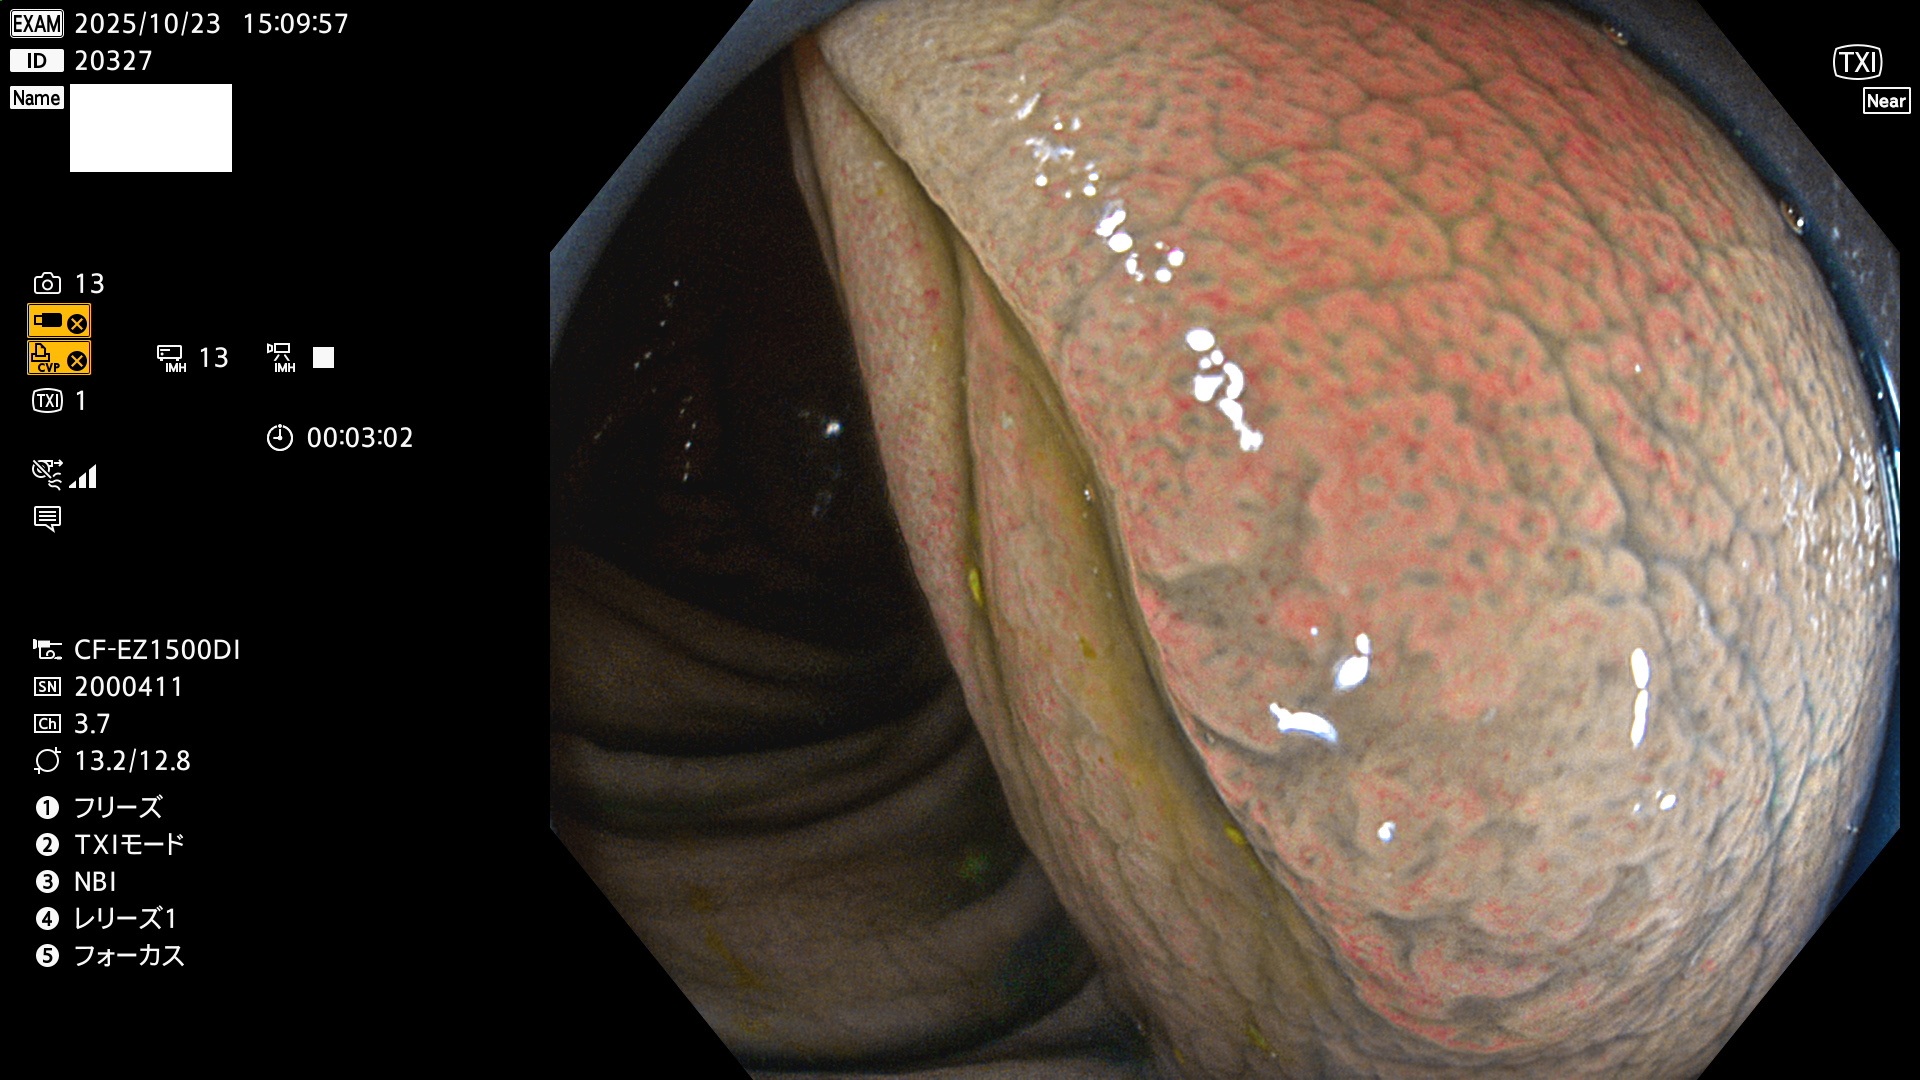

完全に平坦な物をUb、陥凹している物をUcと呼びます。Ubは認識が困難で、Ucはびらん(炎症)と紛らわしいために見落とされやすく、「内視鏡後・大腸癌」の原因になります。

毎週の検査(木・金・土・日)に発見されたUbとUc型・腺腫を、その週の日曜の夜にUPし1週間、提示します。

2025年10月23日〜10月26日の4日間(40件)6個 (Uc_ADR=6個/40人=15%)